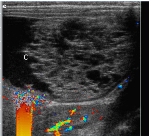

Tất cả bệnh nhân (100%) đều có triệu chứng chính đau bụng; trong khi 33 người (85%) nôn ói; 22 người (56%) có bạch cầu tăng; và 7 người (18%) tăng thân nhiệt. Hầu hết những buồng trứng bị xoắn và phức hợp khối/buồng trứng xoắn đó tăng kích thước. 21 bệnh nhân (54%) có dòng chảy động mạch khi khảo sát trên siêu âm Doppler, và 18 bệnh nhân (46%) không ghi nhận dòng chảy động mạch. 13 bệnh nhân (33%) có dòng chảy tĩnh mạch, và 26 bệnh nhân (67%) không ghi nhận dòng chảy tĩnh mạch. Không có sự khác biệt có ý nghĩa thống kê giữa nhóm tuổi trước dậy thì và tuổi sinh sản về dòng chảy tĩnh mạch và động mạch.

Triệu chứng đau bụng, nôn ói, buồng trứng gia tăng kích thước, và không hiện diện dòng chảy tĩnh mạch tại buồng trứng là những biểu hiện lâm sàng và siêu âm thường thấy nhất của xoắn buồng trứng. Tuy nhiên, buồng trứng gia tăng kích thước, thậm chí hiện diện dòng chảy động mạch và tĩnh mạch, là những triệu chứng đi kèm với xoắn buồng trứng thường gặp nhất trên siêu âm. Nghi ngờ cao xoắn buồng trứng khi bắt đầu có những triệu chứng lâm sàng và sự gia tăng kích thước của buồng trứng, bất kể có hiện diện hoặc không hiện diện dấu hiệu trên siêu âm Doppler.